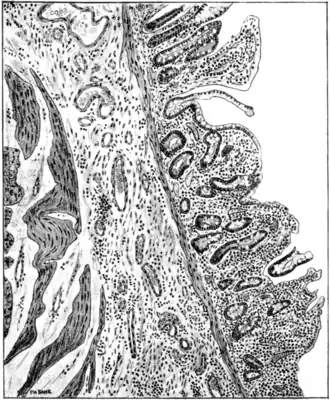

Fig. 83.—Transverse section of ileum in case of sprue, showing partial loss of columnar epithelium (probably a post-mortem change), shrinkage of villi, round-cell infiltration, fibrosis of submucosa, and dilatation of nutrient vessels of submucosa. (Bahr.)